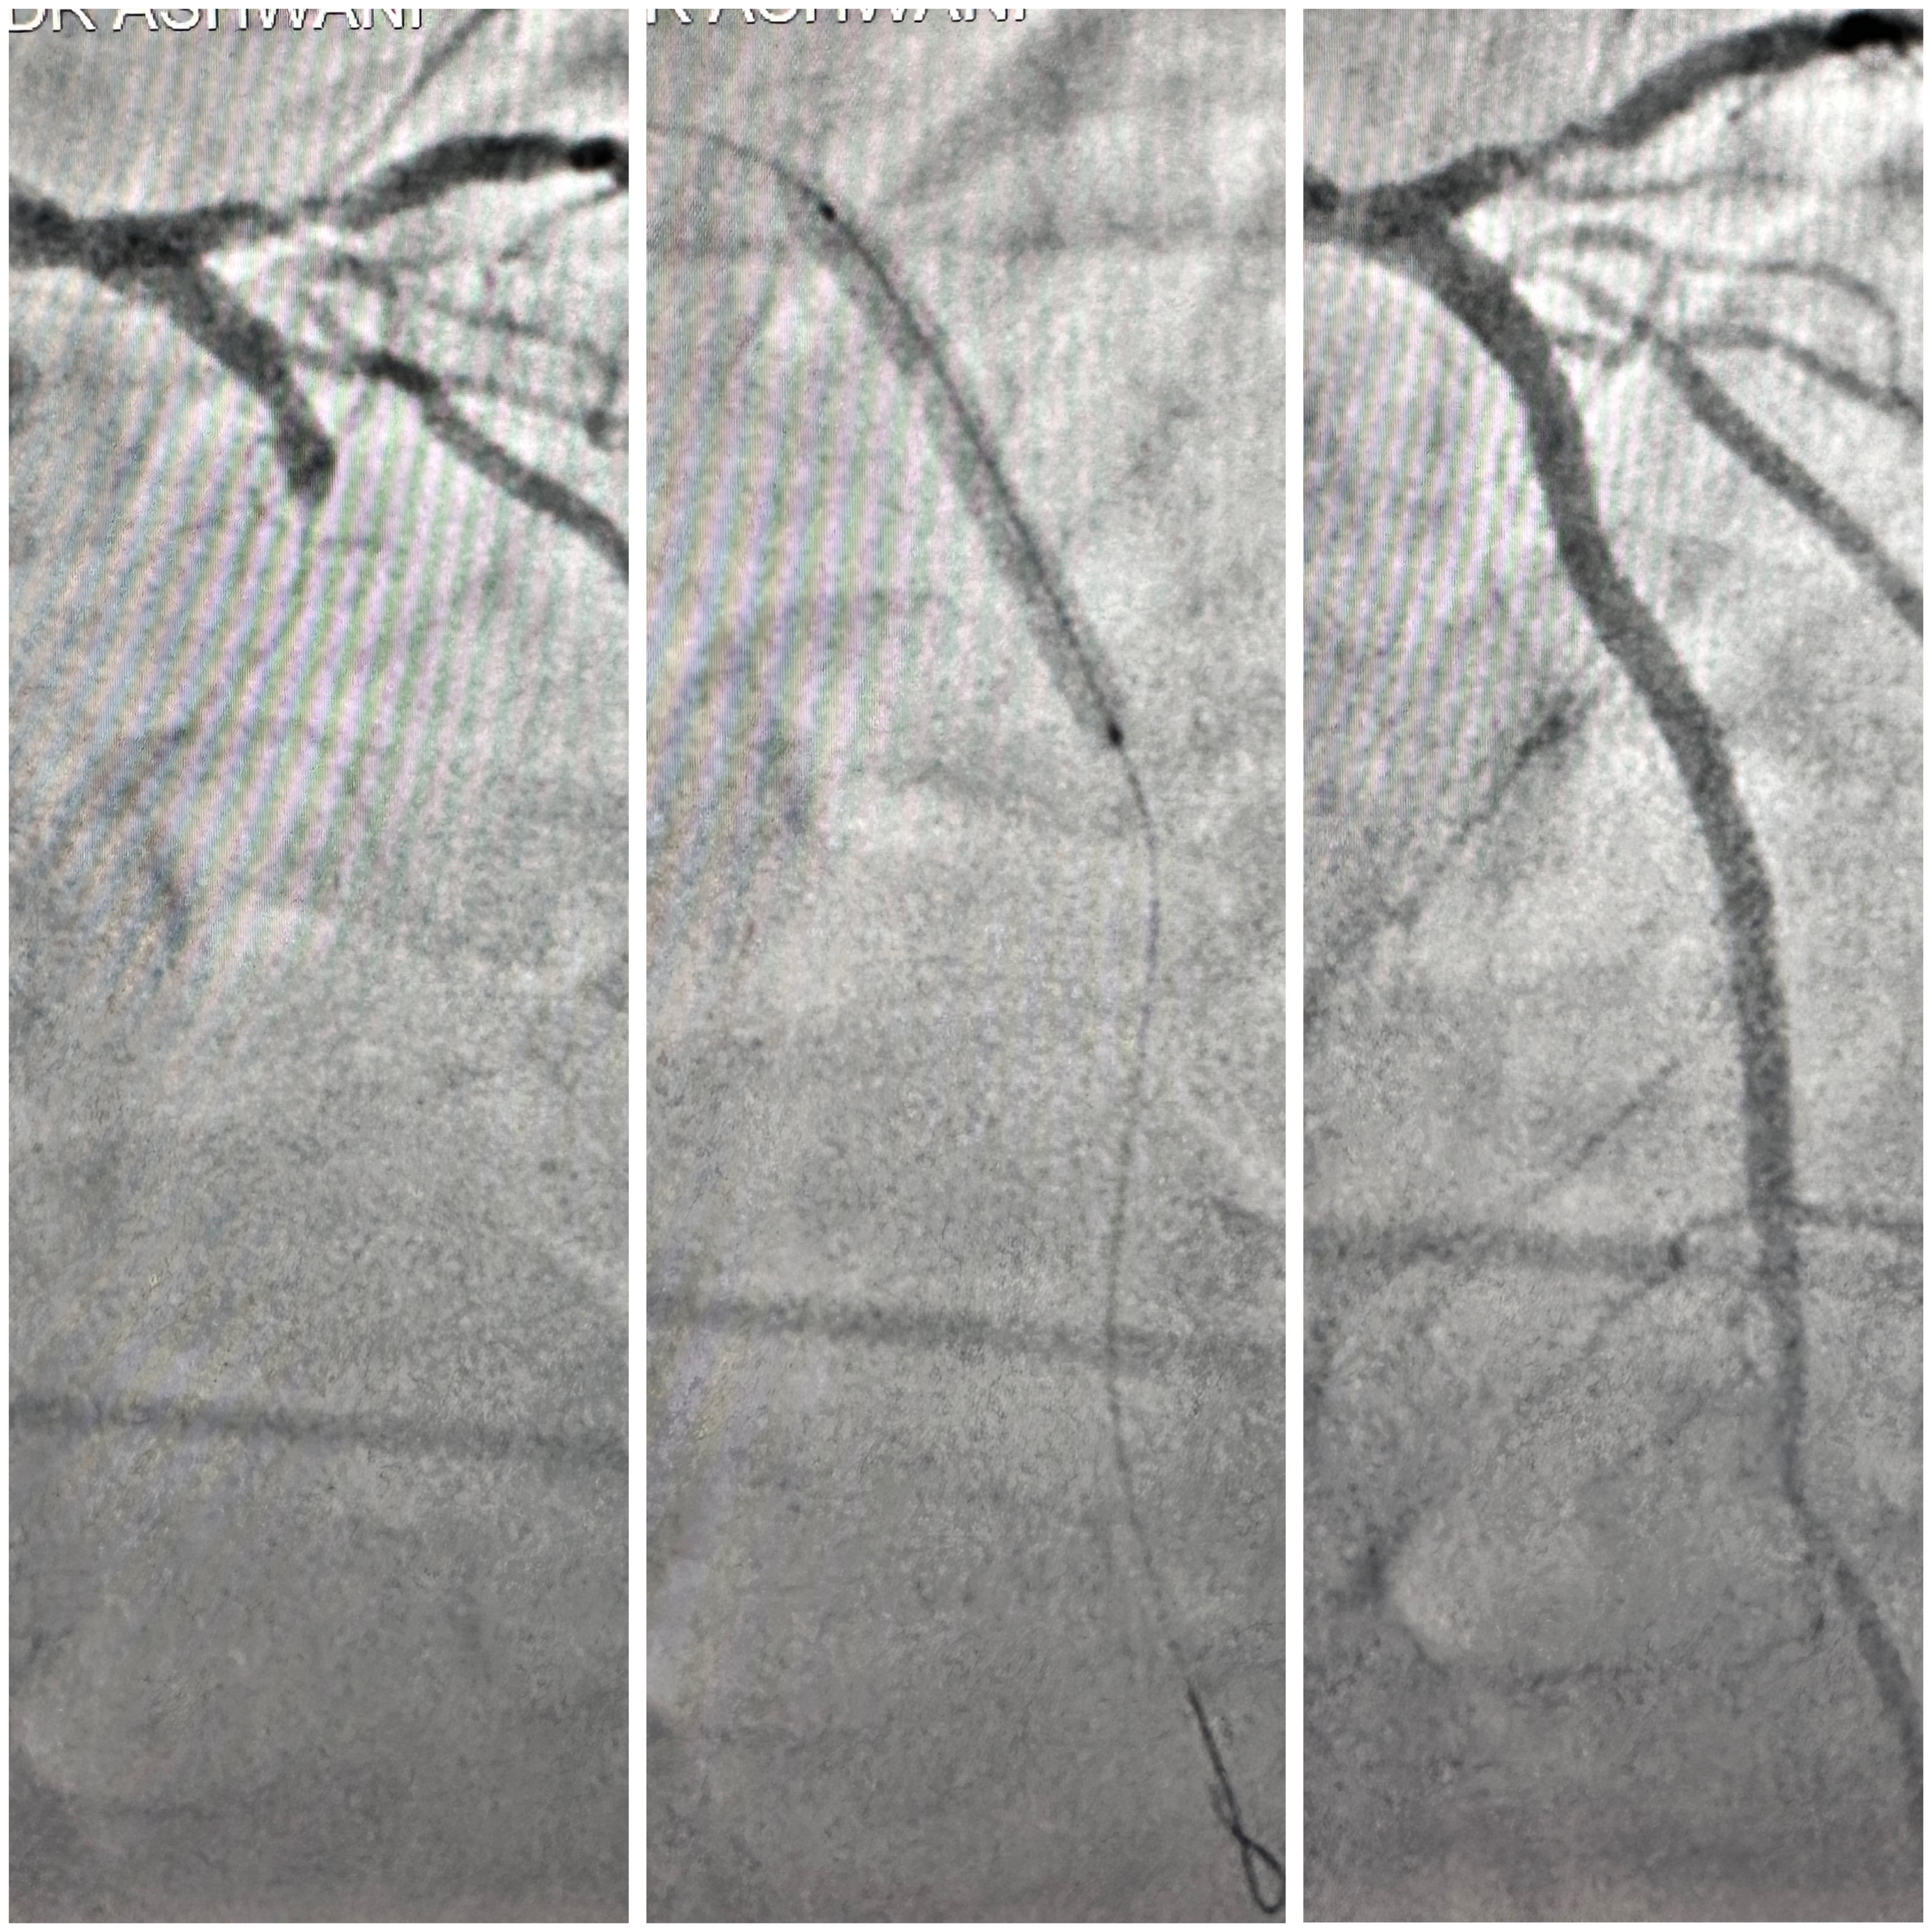

Angioplasty/Stenting

Angioplasty, also called Percutaneous Coronary Intervention (PCI), is a medical procedure used to open narrowed or blocked arteries in the heart. It restores blood flow and helps prevent heart attacks or other cardiac emergencies.

A thin tube called a catheter is inserted through an artery—usually in the groin, wrist, or arm. At the tip of the catheter, there's a small balloon. Once it reaches the blocked artery, the balloon inflates. This pushes plaque against the artery walls, widening the passage.

Step-by-Step: What to Expect

• Preparation: You’ll fast for several hours. The area of catheter insertion is cleaned and numbed.

• Insertion: A catheter is threaded to the coronary artery.

• Balloon Inflation: The balloon expands to push plaque aside.

• Stent Placement: A stent is placed to hold the artery open.

• Completion: The catheter is removed, and the site is bandaged.

The procedure takes 30 to 90 minutes and is done under local anesthesia with mild sedation.